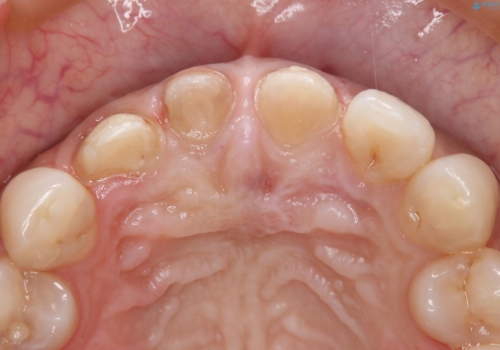

- 1週間ほど前に自転車で転倒して前歯をぶつけた後、歯の色が変わっていることが気になり受診された方です。診察の結果、失活及びエナメル質に多数の亀裂が認められたため、根管処置およびセラミッククラウンによる治療を行いました。元々右上2番目の歯の形が気になっていたとの事で、左右対称の形に近づけるように補綴しました。

左上1番目の歯は失活していませんでしたが、歯の表面に多数の亀裂が認められました。患者様のご希望により、前歯3本をまとめて補綴処置することとなりました。土台となる歯質の色が異なる状態でしたが、熟練した技工士さんの技術により3本とも同じ色味になるように仕上げていただきました。色味、形態ともに自然な被せ物に大変喜んでいただけました。